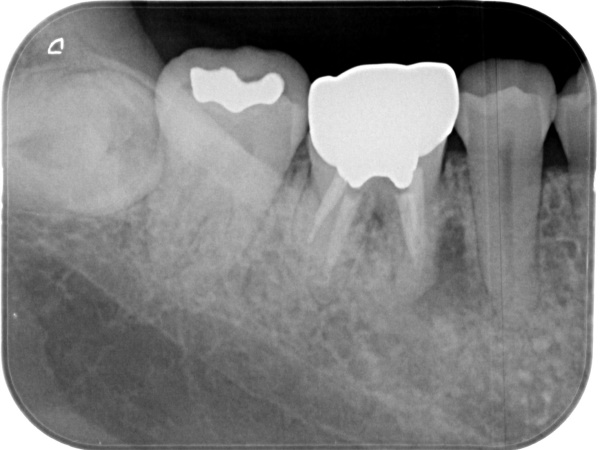

初診時